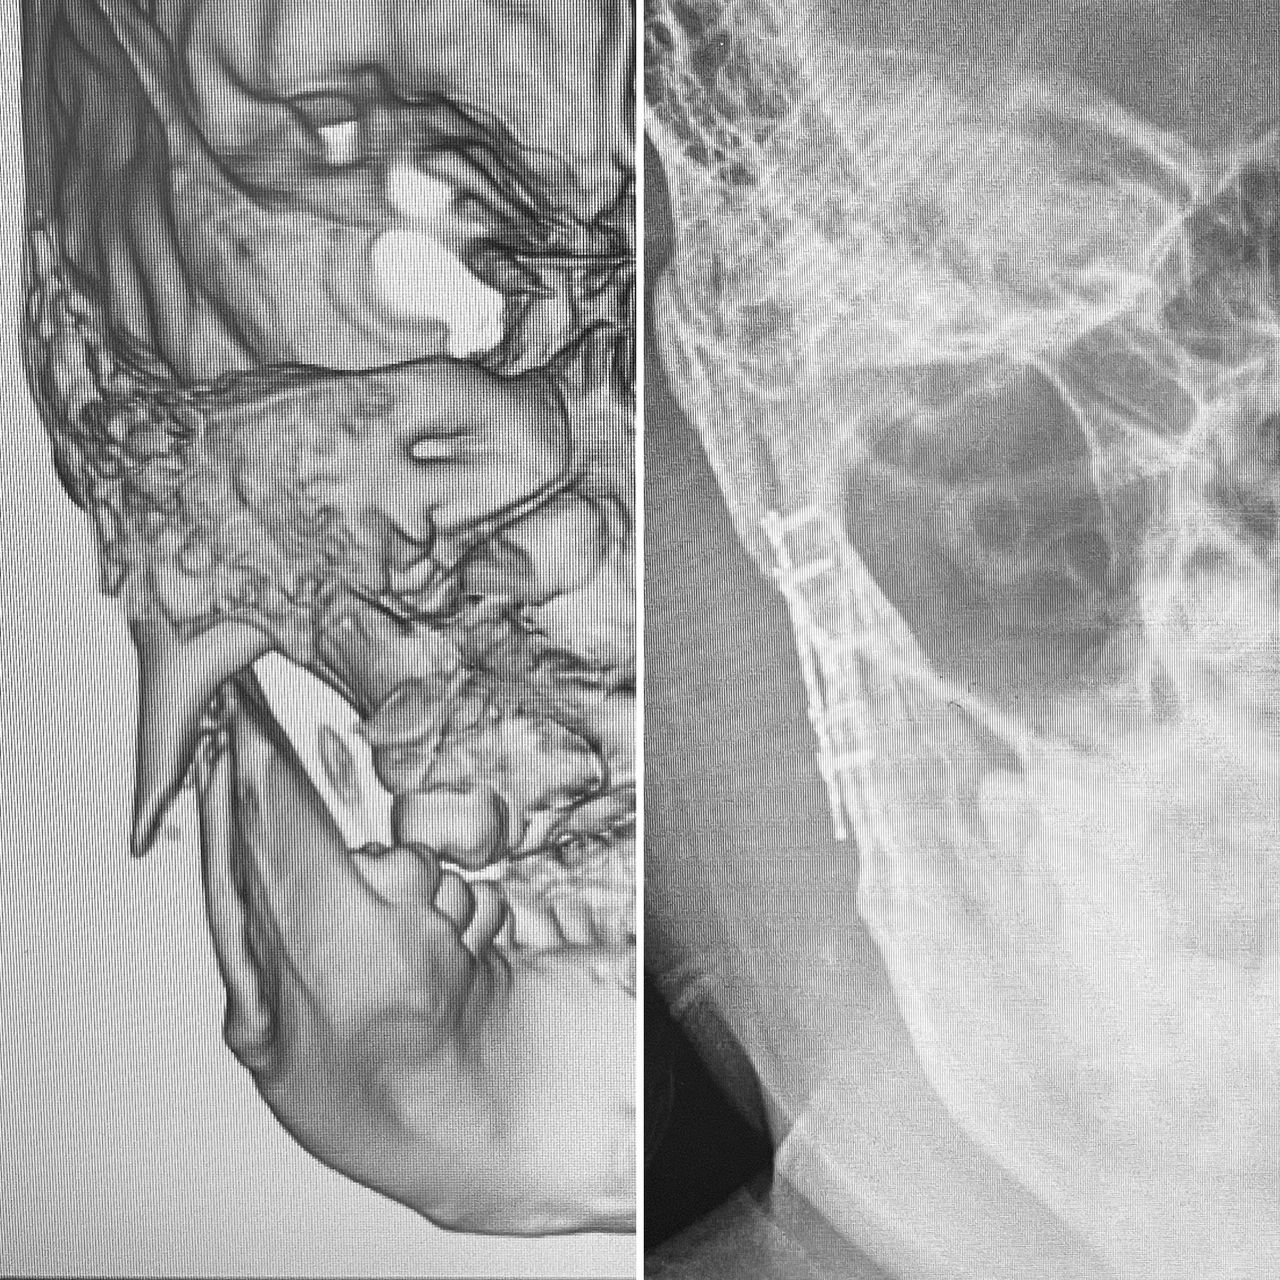

En el área de cirugía maxilofacial tengo experiencia en el manejo quirúrgico de trauma facial, anomalías dento-faciales, disfunción de articulación temporomandibular, reconstrucción de maxilares, Cirugía estetica Facial, blefaroplastia, otoplastia, mentoplastia, Lifting facial, Lip Lift y reposicionamiento labial, retiro de biopolimeros en cara y Armonización Oro-Facial.

In the field of maxillofacial surgery, I have experience in the surgical management of facial trauma, dentofacial anomalies, temporomandibular joint dysfunction, mandibular reconstruction, facial cosmetic surgery, blepharoplasty, otoplasty, mentoplasty, facelifts, lip lifts and lip repositioning, removal of facial biopolymers, and orofacial harmonization.

- Cirugía ortognática